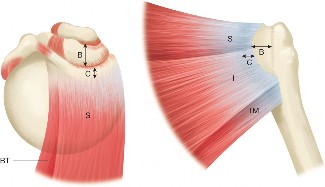

The correct answer is (C). This structure is a thickening of the coracohumeral ligament that starts anteriorly just posterior to the short head of the biceps tendon on the coracoid process, extends posteriorly through the edge of the avascular zone of the supraspinatus and infraspinatus, and ends at the inferior edge of the infraspinatus. One proposed function of the cable is to act like a cable in a suspension bridge, helping to evenly distribute forces on the humeral head produced by the rotator cuff (see Fig. 2–6).

Figure 2–6_Illustration showing the rotator cable and rotator crescent. B, rotator crescent; C, rotator cable; BT, biceps tendon; I, infraspinatus; S, supraspinatus; TM, teres minor. (Redrawn from Burkhart SS, Lo IKY. Arthroscopic rotator cuff repair. _J Am Acad Orthop Surg. 2006;14(6):333–346.)

The rotator crescent (Answer A) is the thin tissue that exists lateral to the rotator cable medial to the attachment of the supraspinatus and infraspinatus. It is composed on the tendons of these two rotator cuff muscles (see Fig. 2–6).